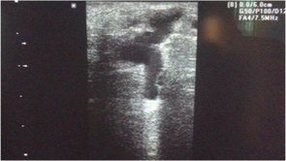

Resim. Perforan vende çap artışı ve dopplerde kaçak

Genel olarak perforan ven çapının 3.5mm ve üzerinde saptanması yetmezlik lehine bir bulgu olarak saptanır. Ayrıca dopplerde geri kaçan akımın görüntülenmesi ve süresi de ciddiyeti hakkında bilgi vermektedir.